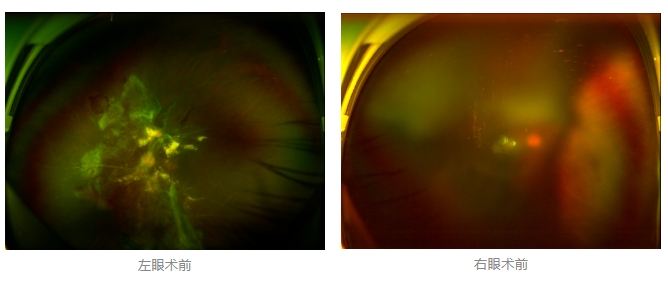

經(jīng)廈門眼科中心眼底病??菩姓魅瓮鯐圆z查后,確診其雙眼糖尿病視網(wǎng)膜病變VI期,伴發(fā)雙眼視網(wǎng)膜脫離和黃斑水腫,且右眼視網(wǎng)膜上增殖膜叢生,若再不盡快進(jìn)行治療,恐有失明風(fēng)險(xiǎn)。

面對(duì)陳先生的復(fù)雜病情,王曉波主任采用玻璃體切割術(shù)聯(lián)合膜切除術(shù)等方式,精細(xì)剝離牽拉視網(wǎng)膜的增殖膜,復(fù)位脫離的視網(wǎng)膜,同時(shí)進(jìn)行玻璃體腔注藥促進(jìn)黃斑水腫吸收。

經(jīng)過規(guī)范化治療,術(shù)后2個(gè)月復(fù)查時(shí)陳先生的視力已有明顯改善,矯正視力從眼前指數(shù)提升至0.3,成功擺脫“失明危機(jī)”。但王曉波主任強(qiáng)調(diào):“這只是階段性勝利,后續(xù)治療不能松懈。”